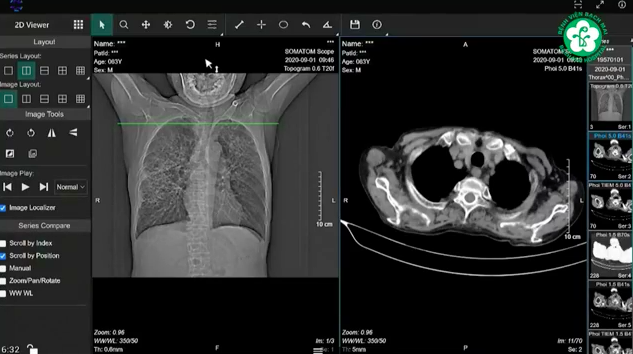

Khám chữa bệnh từ xa: Hành trình “giành giật” hơi thở cho nam bệnh nhân 6 lần tim ngừng đập - Ảnh 3.

Hình ảnh cắt lớp vi tính tình trạng ngực, tim của bệnh nhân P.

Qua chẩn đoán hình ảnh, PGS.TS Nguyễn Ngọc Quang – Phó Viện trưởng Viện Tim mạch (Bệnh viện Bạch Mai) nhận định: “Nếu chúng ta bàn về câu chuyện mạch vành đơn thuần thì tổn thương sau nhồi máu cơ tim cấp tuần thứ 2 sẽ có tình trạng suy tim sau nhồi máu. Tất nhiên tình trạng suy tim này đã khá hơn so với trước đó. Tuy nhiên, qua hình ảnh của Bệnh viện Đa khoa tỉnh Phú Thọ cung cấp thì quả tim của bệnh nhân gần như đã lờ đờ, không bóp một chút nào cả. Vấn đề đặt ra lúc này là chiến lược can thiệp mạch vành phụ thuộc khá nhiều vào tình trạng suy tim, suy thận”.